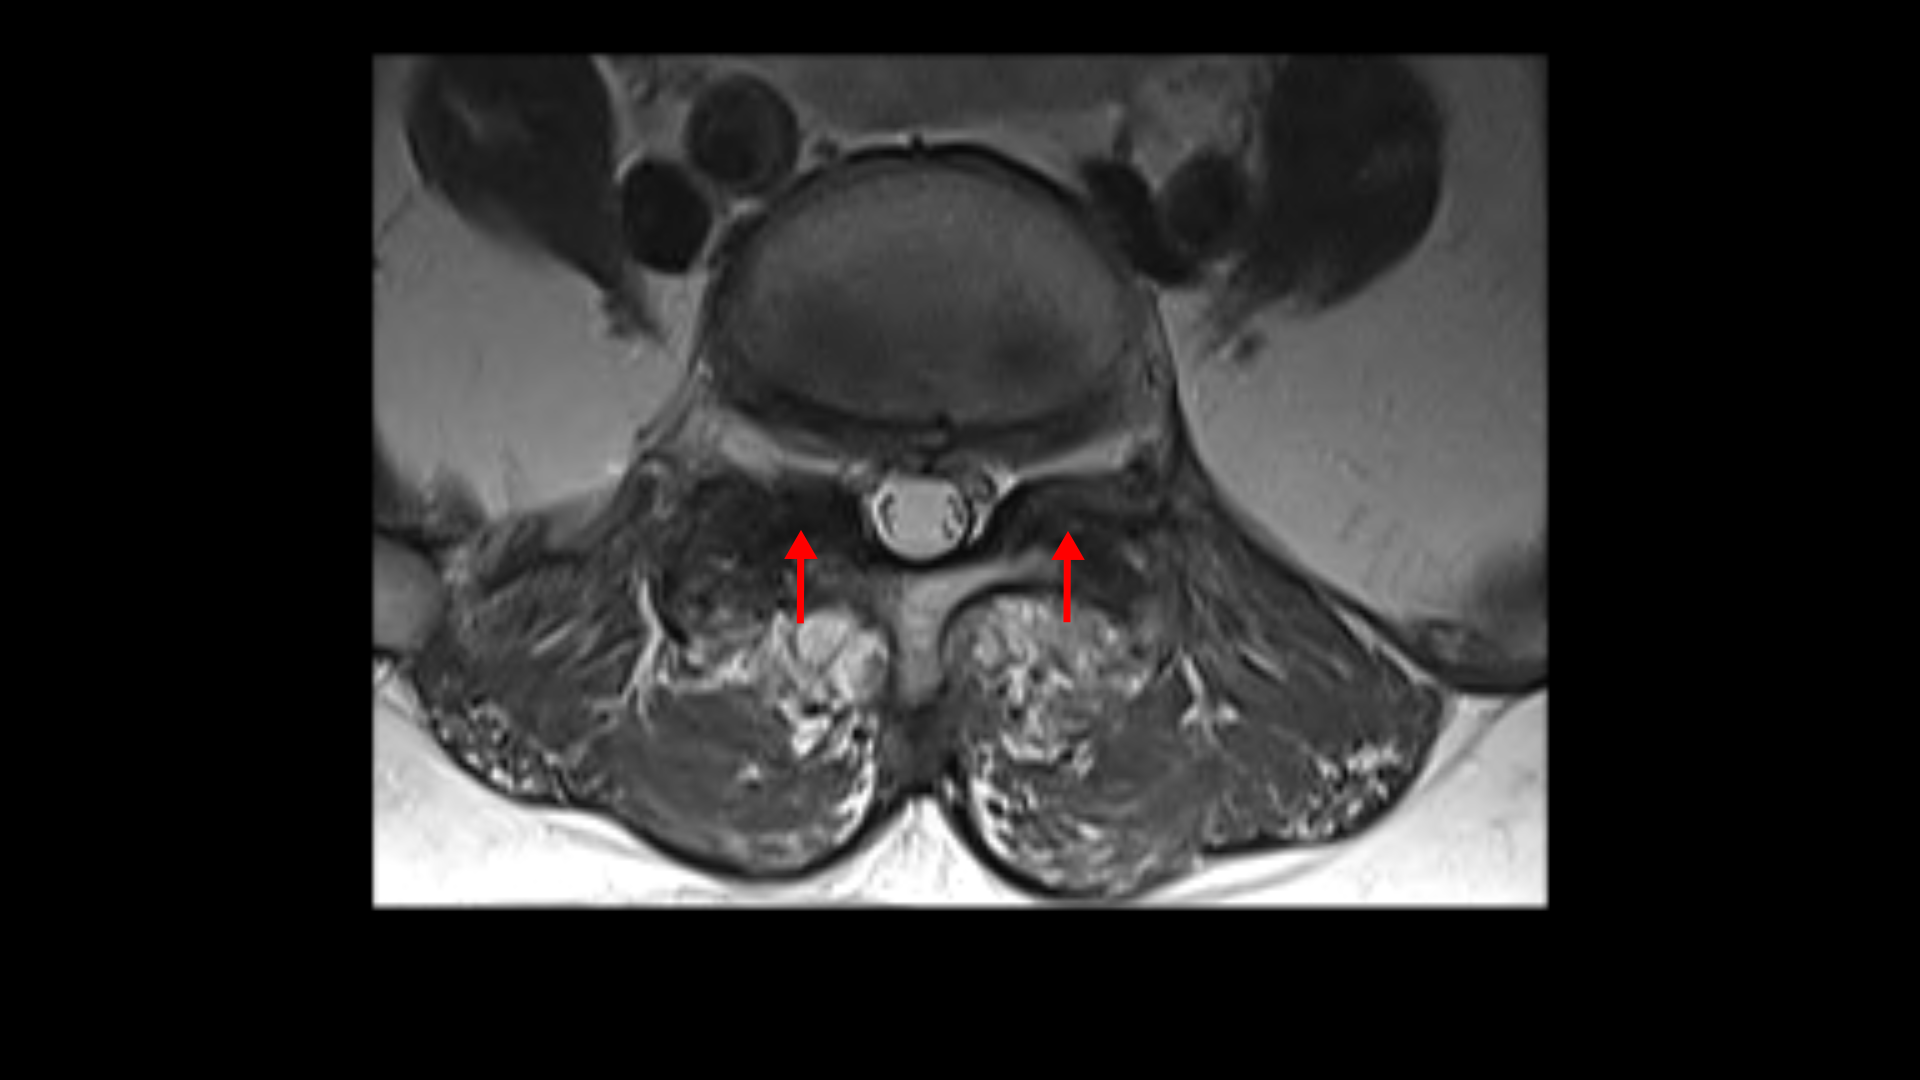

먼저 5번 1번에 척추관 내의 황색인대의 골화 현상이 보이고

후관절의 퇴행도 심해 보입니다.

또 흉추 두 마디에서도 역시 황색인대의 골화 현상이 보입니다.

그리고 허리 4마디에 퇴행성 허리디스크가 있습니다.